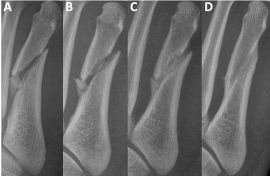

On examination, there was focal tenderness over the dorsal lateral forefoot without gross deformity, open wounds, or sensory deficits. Vascular status was grossly intact. Three views of non-weight-bearing radiographs revealed a mildly comminuted mid-diaphyseal fifth metatarsal fracture with a small angulated butterfly fragment (Figures 1A, 2A, and 3A). On the oblique view there was approximate 3.59mm of gapping noted with 3 distinct fracture fragments. Some shortening of distal metatarsal was apparent as well. The patient was placed in a controlled ankle motion (CAM) boot, provided with crutches, and instructed to remain non-weight-bearing.

One month after the initial injury, swelling and ecchymosis had resolved, and pain was improved. He was able to weight-bear in the CAM boot without difficulty. Follow-up weight-bearing radiographs showed stable alignment with no interval displacement (Figures 1B, 2B, and 3B). We advised him to advance to weight-bearing as tolerated in supportive shoe gear after 2 additional weeks.

At the 4 month mark, weight-bearing radiographs demonstrated osseous bridging across the fracture site (Figures 1C, 2C, and 3C). By 11 months, the patient was pain-free and had returned to full activity. Non-weight-bearing radiographs confirmed complete fracture union with preserved joint spaces and no deformity (Figures 1D, 2D, and 3D). At 16 months, he remained asymptomatic with normal activities of daily living.